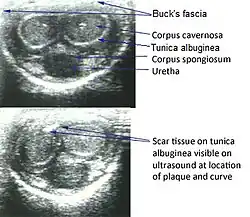

Peyronie's disease diagnosis is mostly clinical. Patient history and physical examination are crucial. The most prominent features are acquired penile curvature, palpable plaques, erectile dysfunction, and pain during erections. Penile ultrasonography is the imaging method of choice for plaque location, measurement, and confirmation of calcification. Doppler ultrasound can be utilized to assess vascular function, which is useful in the evaluation of associated erectile dysfunction. Imaging also helps to differentiate PD from congenital penile curvature, penile fracture, or neoplastic disease. MRI can be employed in severe ones, although it is generally not required.[13]

Ultrasonography

On penile ultrasonography, the typical appearance is hyperechoic focal thickening of the tunica albuginea. Due to associated calcifications, the imaging of patients with Peyronie's disease shows acoustic shadowing, as illustrated in figures below. Less common findings, attributed to earlier stages of the disease (still mild fibrosis), are hypoechoic lesions with focal thickening of the paracavernous tissues, echoic focal thickening of the tunica without posterior acoustic shadowing, retractile isoechoic lesions with posterior attenuation of the beam, and focal loss of the continuity of the tunica albuginea.

In the Doppler study, increased flow around the plaques can suggest inflammatory activity and the absence of flow can suggest disease stability. Ultrasound is useful for the identification of lesions and to determine their relationship with the neurovascular bundle. Individuals with Peyronie's disease can present with erectile dysfunction, often related to venous leakage, due to insufficient drainage at the site of the plaque. Although plaques are more common on the dorsum of the penis, they can also be seen on the ventral face, lateral face, or septum.[14]